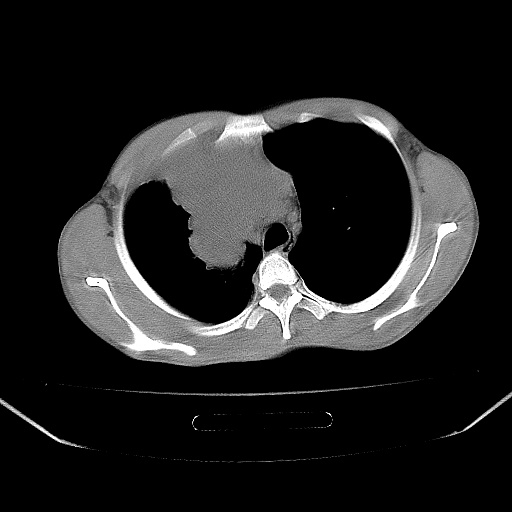

以下是引用zjzjr在2008-7-20 12:57:00的发言:[br]考虑为生殖源性肿瘤(内胚窦瘤),侵袭性胸腺瘤可能性大;右侧少量胸腔积液。

以下是引用xinliheng001在2008-7-20 21:17:00的发言:[br]右纵隔巨大分叶状软组织均质密度肿块,右上肺叶受压明显,纵隔右移、胸膜受累有少量积液和结节样增厚。应增强扫描一定会有更具诊断价值的信息。

以下是引用xinliheng001在2008-7-20 21:17:00的发言:[br]右纵隔巨大分叶状软组织均质密度肿块,右上肺叶受压明显,纵隔右移、胸膜受累有少量积液和结节样增厚。应增强扫描一定会有更具诊断价值的信息。